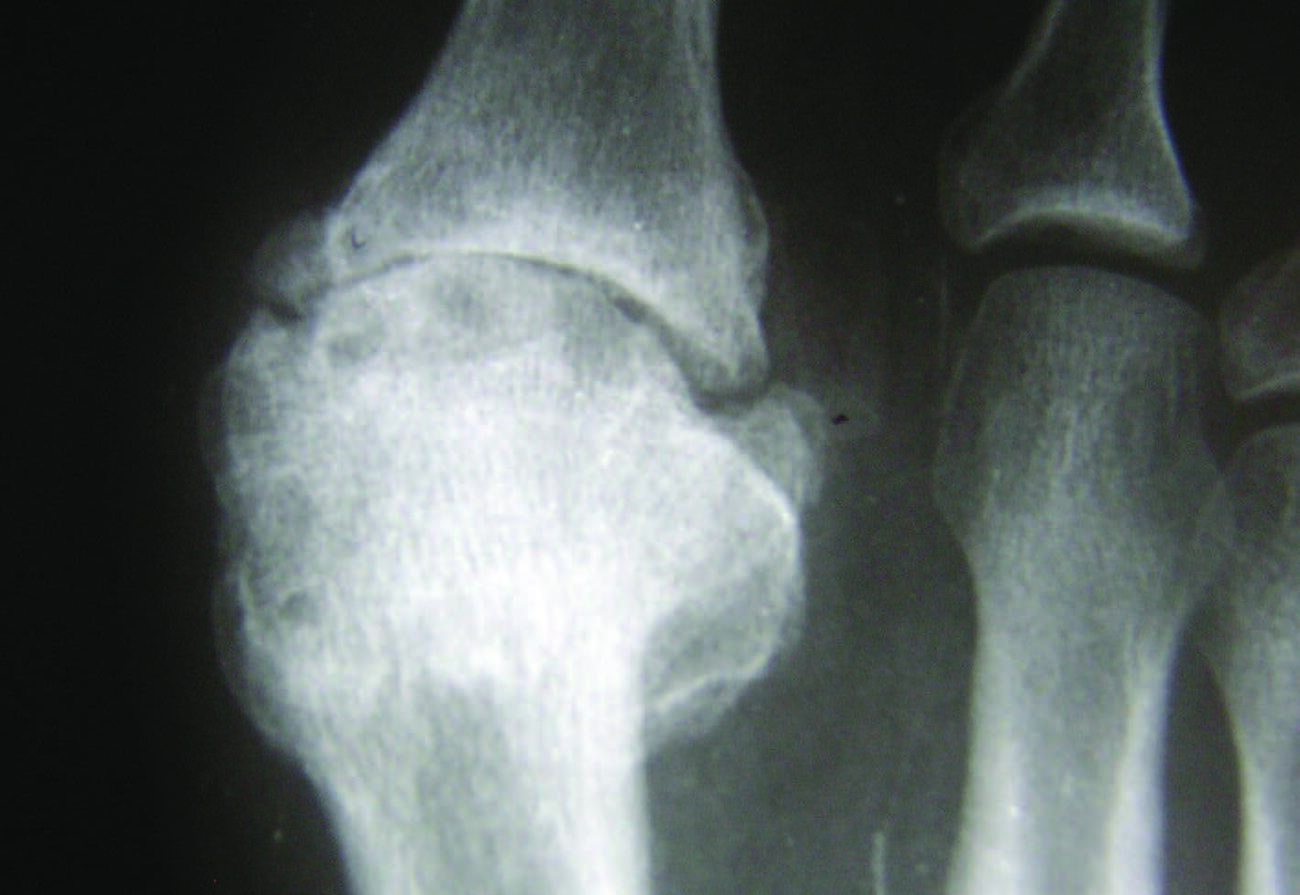

Stage 3. In stage 3, the patient has lost nearly all motion in the first MPJ, now with less than 10 degrees of dorsiflexion remaining, and movement of the joint to the end range of motion causes the patient significant pain.17 Radiographically, there will be significant joint space narrowing, joint destruction, and with possible sesamoid change. This stage by definition constitutes a hallux rigidus.

Stage 4. This stage is similar to stage 3, except any motion at the first MPJ causes the patient pain.17 Radiographs will demonstrate arthrosis of the joint, with osteophytic changes of both the metatarsal head, and base of the proximal phalanx.

Radiographic findings may be subtle or negative in the early phases of the condition.18 As the condition progresses, radiographic findings may reveal joint narrowing, thinning of articular surfaces, osteophytic changes of the base of the proximal phalanx, spurring of the metatarsal head, and possible fracture fragments/loose bodies. If previous injury to the sesamoids occurred, there may be degenerative changes there as well.18

Preoperative radiographs will not always accurately indicate the amount of articular destruction, therefore it is imperative at the time of surgery to visually inspect the articular surface of the first metatarsal head. There may be more or less articular loss than expected by the level of narrowing of the joint space. Often I find the sesamoid apparatus will be “frozen” to the plantar surface of the first metatarsal due to previous injury or fibrosis. After resection of dorsal osteophytes, debridement of chronic synovitis and careful freeing of the sesamoids, the surgeon can re-evaluate the amount of dorsiflexion of the first MPJ. Subchondral drilling may assist where “denuded” cartilage of the metatarsal head is evident.22 Restoration of the articular surface may take place via transplant autograft tissue.23,24 However, there are no reported studies of this advanced procedure in the runner population.